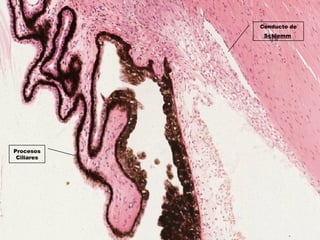

Conducto de

Schlemm

Procesos

Ciliares

Procesos Ciliares

Cuerpos Ciliares

Musculo Ciliar